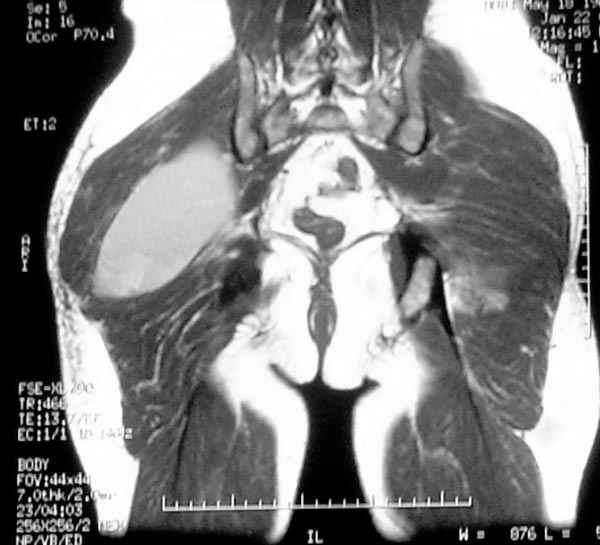

Уважаемые коллеги,Неоднократные пункционные эвакуация (3 раза) крови изягодичной области, после полученной пройзводственнойтравмы (более 1.5 мес) ударом в ягодицу тяжелым, около полутонны предметом.

Рентгенограмма без особенностей, несмещенные переломы лонной и седалищных костей таза.Последная пункция 10 дней назад 180 мл темной крови, после пункции сделано магнито-резонансные исследование (на снимках), какой диагноз и тактика дальнейшего лечения, какие рекомендации?Джолдас Кульджанов

Разбираемый случай немного отличался от классического Degloving Injury

или Morel-Lavalle Lesion, которые часты при переломах ацетабулума и

костей таза. Состояние, наблюдаемое после удара, в результате чего

образуются обширные полости в тазобедренной области: ягодицы или

большого вертела. Как описал Анатолий, обширные полости заполняются

кровью, затем синовиальной жидкостью, отодвигают сроки операции или

после операции приводят к осложнениям послеоперационных ран.

Описанный случай:

В промежутке около месяца 3 пункции с удалением около 180 мл крови

каждый раз. После исследовании МРТ было принято решение - удаление

гематомы в операционной более широким доступом. Во время операции -

под ягодичной мышцей была капсула, где скопилось около 700 мл

гематомы, после удаления в полости обнаружили несколько закупорившихся

вен и краевой разрыв одной из двух ветвей нижней ягодичной артерии.

После промывания, гемостаза и дренажа, по рекомендации хирурга стенку

полости обработали спреем Tisseel, специальным склерозирующим

препаратом, применяемым пластическими хирургами, затем зашили рану.

Дренажи удалены на 5 день, рана зажила первично. Случай был интересен

применением препарата Tisseel Fibrin Sealant для склерозирования

полостей, только недавно получившим разрешение к применению, хотя по

аннотации в Европе и в Южной Америке применяют давно.